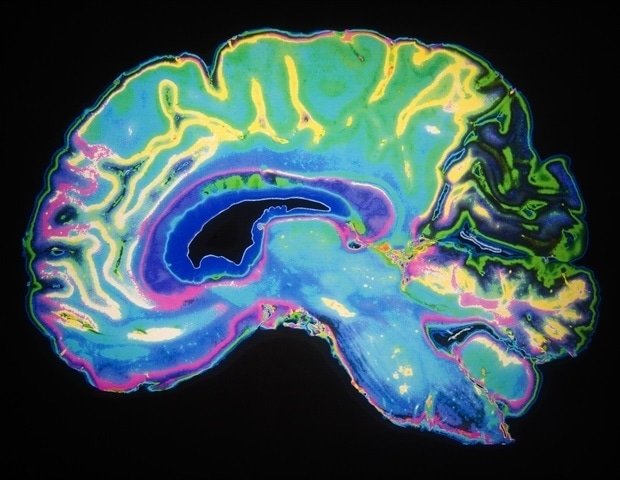

Alzheimer’s disease begins when a sticky protein called amyloid beta builds up in the brain, forming plaques, triggering a cascade of events that causes brain atrophy and cognitive decline. Microglia, immune cells found in the brain, are responsible for removing waste from the brain, but they can malfunction if overwhelmed in the context of neurodegenerative diseases.

To ease the cleaning burden on microglia, first author Yun Chen, Ph.D., then a graduate student in the lab of Colonna and David M. Holzman, MD, Barbara Burton, Ph.D., and Ruben M. Morris III Distinguished Professor of Neurology at WashU Medicine, turned astrocytes, the most abundant cell type in the brain, into amyloid cleaning machines. He custom designed a gene encoding a chimeric antigen receptor (CAR) and delivered it to astrocytes via a harmless virus injected into mice. The CAR, now present on the surface of astrocytes, enabled the cells to capture and engulf amyloid beta protein. Astrocytes (generally responsible for keeping the brain in order) used their newly acquired abilities to focus solely on clearing amyloid-beta plaques in mice, where they tend to accumulate.

As young mice aged, CAR astrocytes prevented the development of amyloid beta plaques. At about six months of age, when the brains of untreated mice are normally saturated with harmful plaques, the brains of the treated mice were free of plaques. Meanwhile, older mice with saturated brain plaques at the time of treatment had a 50% reduction in the amount of amyloid beta plaques compared to mice injected with a virus lacking the CAR gene.